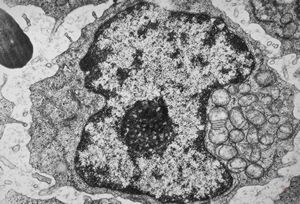

F,51y. | blood - chronic lymphatic leukemia … prolymphocyte